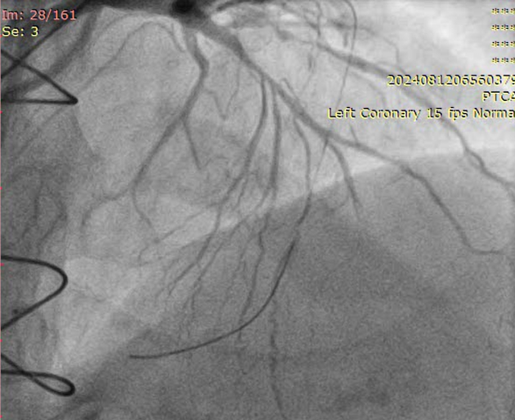

LMCA: distal mild stenosisLAD: diffusely disease from proximal part with total occlusion in mid part with competitive fillingD1, Ramus, OM1- total occlusionLCX: mild diffuse disease RCA: CTO from proximal part, retrograde filling from LADLIMA to LAD: patentSequential LIMA - RIMA “Y” to OM1 to PDA: occludedSequential RSVG to ramus to PLV branch of RCA- occluded

RSVG to Ramus to PLV was engaged with 7F AR-1 guide catheter. Occluded segment in RSVG crossed with Pilot-150 PTCA wire with Caravel micro-catheter and parked into distal RCA. Position of the wire and micro-catheter confirmed with retrograde injection from native LMCA. Retrograde wiring was attempted with Gaia NexT-2, Pilot-150, Pilot-200 PTCA guide wires, but was unsuccessful. Native RCA was engaged with 7F AL 0.75 guide catheter and antegrade wiring was attempted with micro-catheter support and Gaia NexT-2, Pilot-150 followed by Pilot-200 PTCA guide wires, but was unsuccessful. Balloon dilatation was done in proximal RCA with 2.0 x 10 mm SC balloon. Knuckle wire technique was used to cross the lesion from antegrade site but unsuccessful. Finally, lesion crossed with Asahi Gladius MG-14 wire from antegrade approach and wire parked into the RSVG. Micro-catheter exchanged. Serial predilatation was done with 0.75 x 8 mm SC balloon followed by 2.0 x 20 mm SC balloon. IVUS run was taken for vessel size estimation. 3.0 x 48mm DES was deployed from proximal RCA. Post dilatation was done with NC 3.5 x 8 mm balloon. Distal RCA was addressed with 2.75 x 30 mm DEB. Mid RCA was stented with DES 3.00 x 32 mm. Post-dilated with 3.0 x 10 mm NC balloon followed by 3.75 x 8 mm NC balloon. Post-stenting IVUS run showed good stent expansion and apposition. Distal TIMI-III flow was achieved.